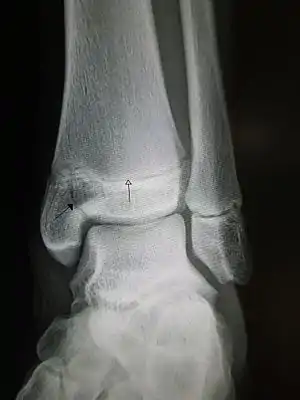

An X-ray of the left ankle showing a Salter–Harris type III fracture of medial malleolus. Black arrow demonstrates fracture line while the white arrow marks the growth plate.